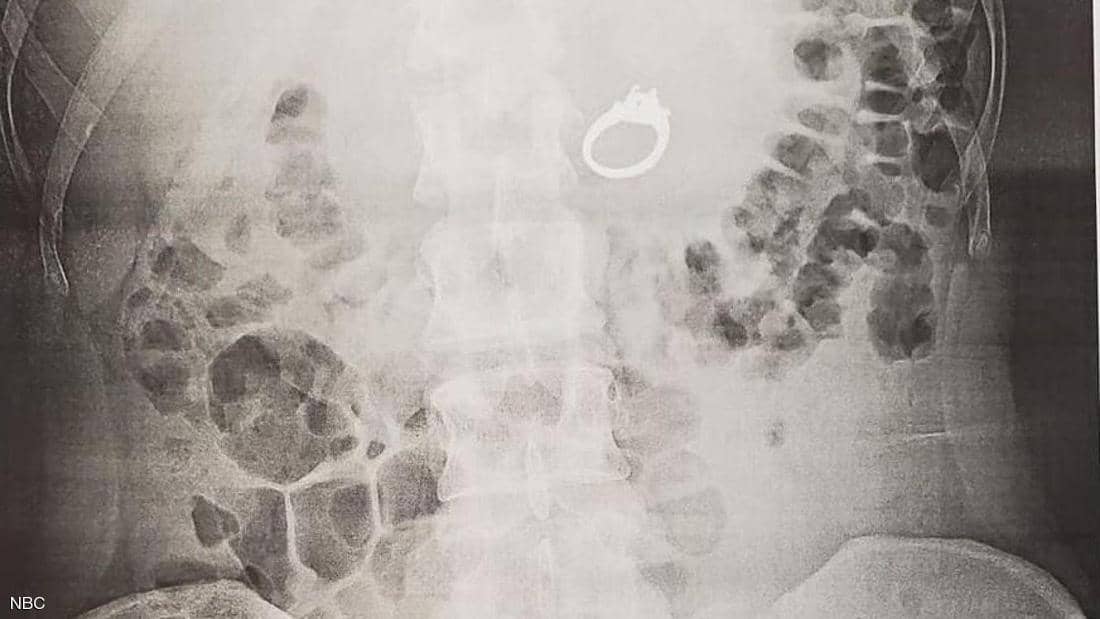

وأضافت أنها كانت تروي بصعوبة ما حدث إلى الأطباء، وقالت: “كنت أضحك و أبكي بشدة”، وفق ما اوردت “هيئة الإذاعة البريطانية”، ورصد فحص بالأشعة السينية وجود خاتم 2.4 قيراط في المعدة، واتفق الأطباء على أنه لن يكون من الحكمة تركه هكذا.